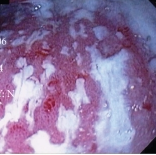

Ενδοσκοπική εικόνα της θήκης. Παρουσία μεγάλων ποσοτήτων βλέννας και ψευδομεμβρανών (Ευγενική παραχώρηση Dr. V. Penopoulos)